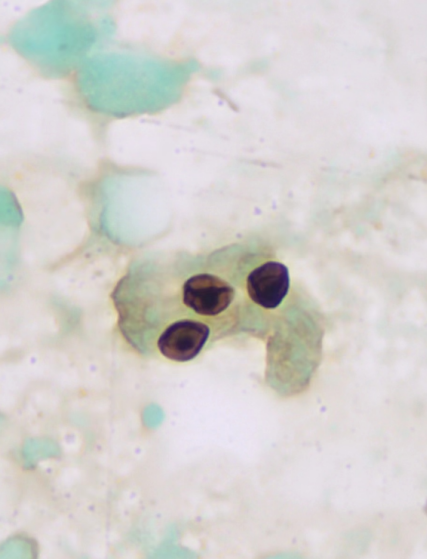

涂片镜检中看见菌体包囊壁呈黑色,呈“双眼皮样”、“括号样”或中心点状深染的形态,可报告:六铵银染色染色阳性(+)检见肺孢子菌。